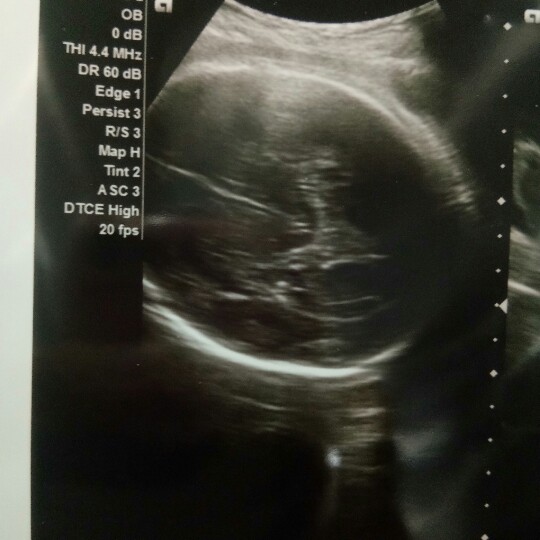

29+2W ชายค่ะ